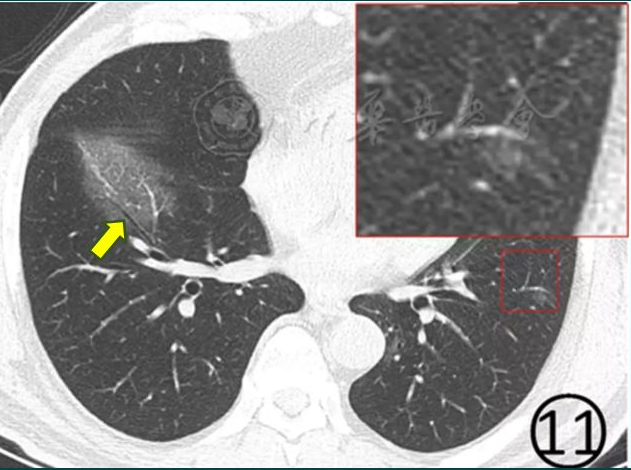

影像进展新冠肺炎的ct典型和不典型表现以及影像学分期

新型冠状病毒肺炎肺部ct特征

新冠肺炎影像学特征